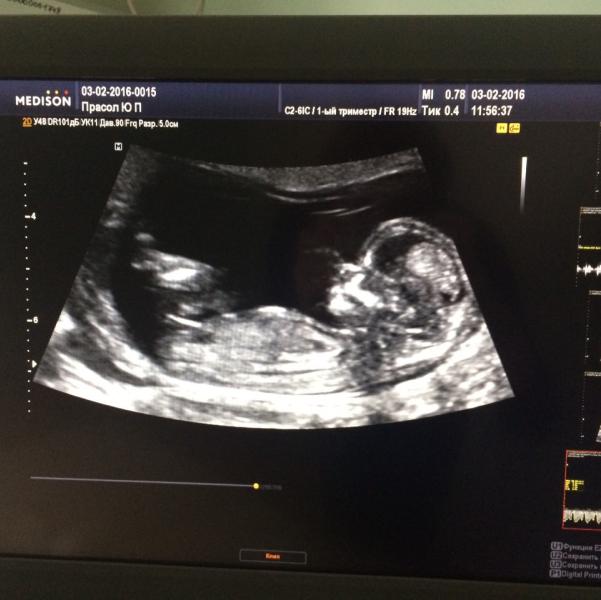

Сегодня у нас был первый скрининг ... О, это непередаваемое чувство ☺️наш любименький малыш 💋💋💋😻

поздравляю;))сама радостная вышла после первого скрининга!))) вам хоть снимок дали :))) а я пролетела ((

@valentinka0608, да , на тел разрешила сфоткать. Даже специально на лучшую позу выбрали 😊почему вам не разрешили ?

@valentinka0608, спасибо ☺️ничего не дали 😏это я на телефон сфоткала 😄